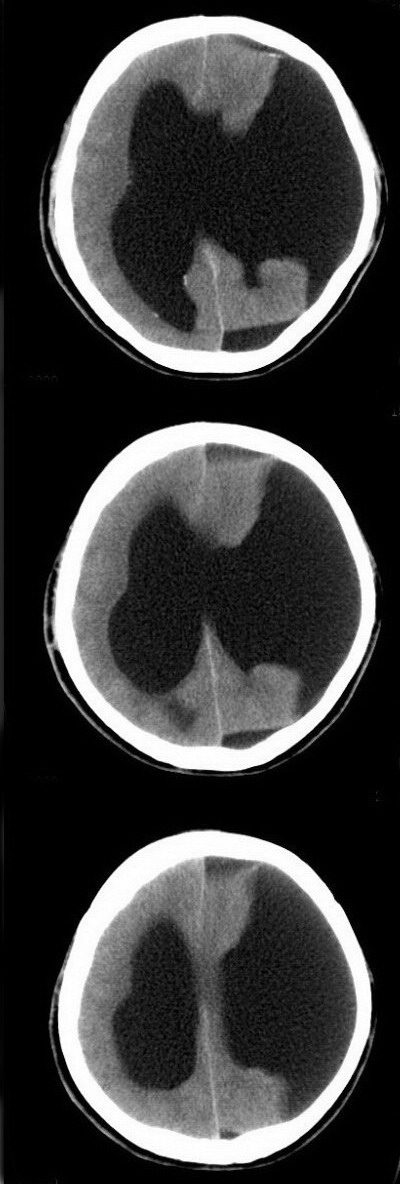

标题: CT16833:F34Y,左侧积水型无脑畸形?请指教. [打印本页]

标题: CT16833:F34Y,左侧积水型无脑畸形?请指教.

女.34.自幼右下肢跛行.智力正常,未发现其它不适。

本例视间隔缺如,基底灰质核团移位,左侧大脑实质较多,能活到这么大还智力正常,多考虑大脑发育不良伴脑积水,积水型无脑畸形一般实质较少而且活不大,智力低下

左侧脑裂畸形(完全型、分离型)。

幕上大脑实质存在,密度正常,智力正常--------不支持无脑畸形

考虑----脑裂畸形或脑积水

左侧脑裂畸形